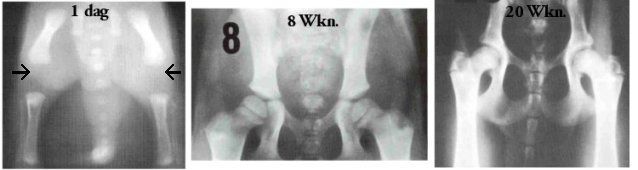

Op deze foto's ziet u de heupen van een pup. Links de eerste levensdag: de heupen en de dijbeenbotten raken elkaar nog niet. Het bekken is nog nauwelijks ontwikkeld. Dat is nodig, anders zou de pup niet geboren kunnen worden. Uiterste flexibiliteit van het hele lichaam is nodig om door het geboortekanaal te passen!

Wanneer de pup 8 weken is, begint het al enigszins op een heupgewricht te lijken, maar echt gevormd is het nog niet. Zo zien de heupen er dus uit als u uw pup meekrijgt: geen wonder dat ze dan nog wankel op de pootjes staan! En nu begrijpt u meteen waarom u voorzichtig moet zijn met uw pupje: het zit nog niet zo stevig in elkaar allemaal!

Op de rechterfoto ziet u de heupen van een jonge hond van 20 weken. Het is nu een min of meer compleet heupgewricht.